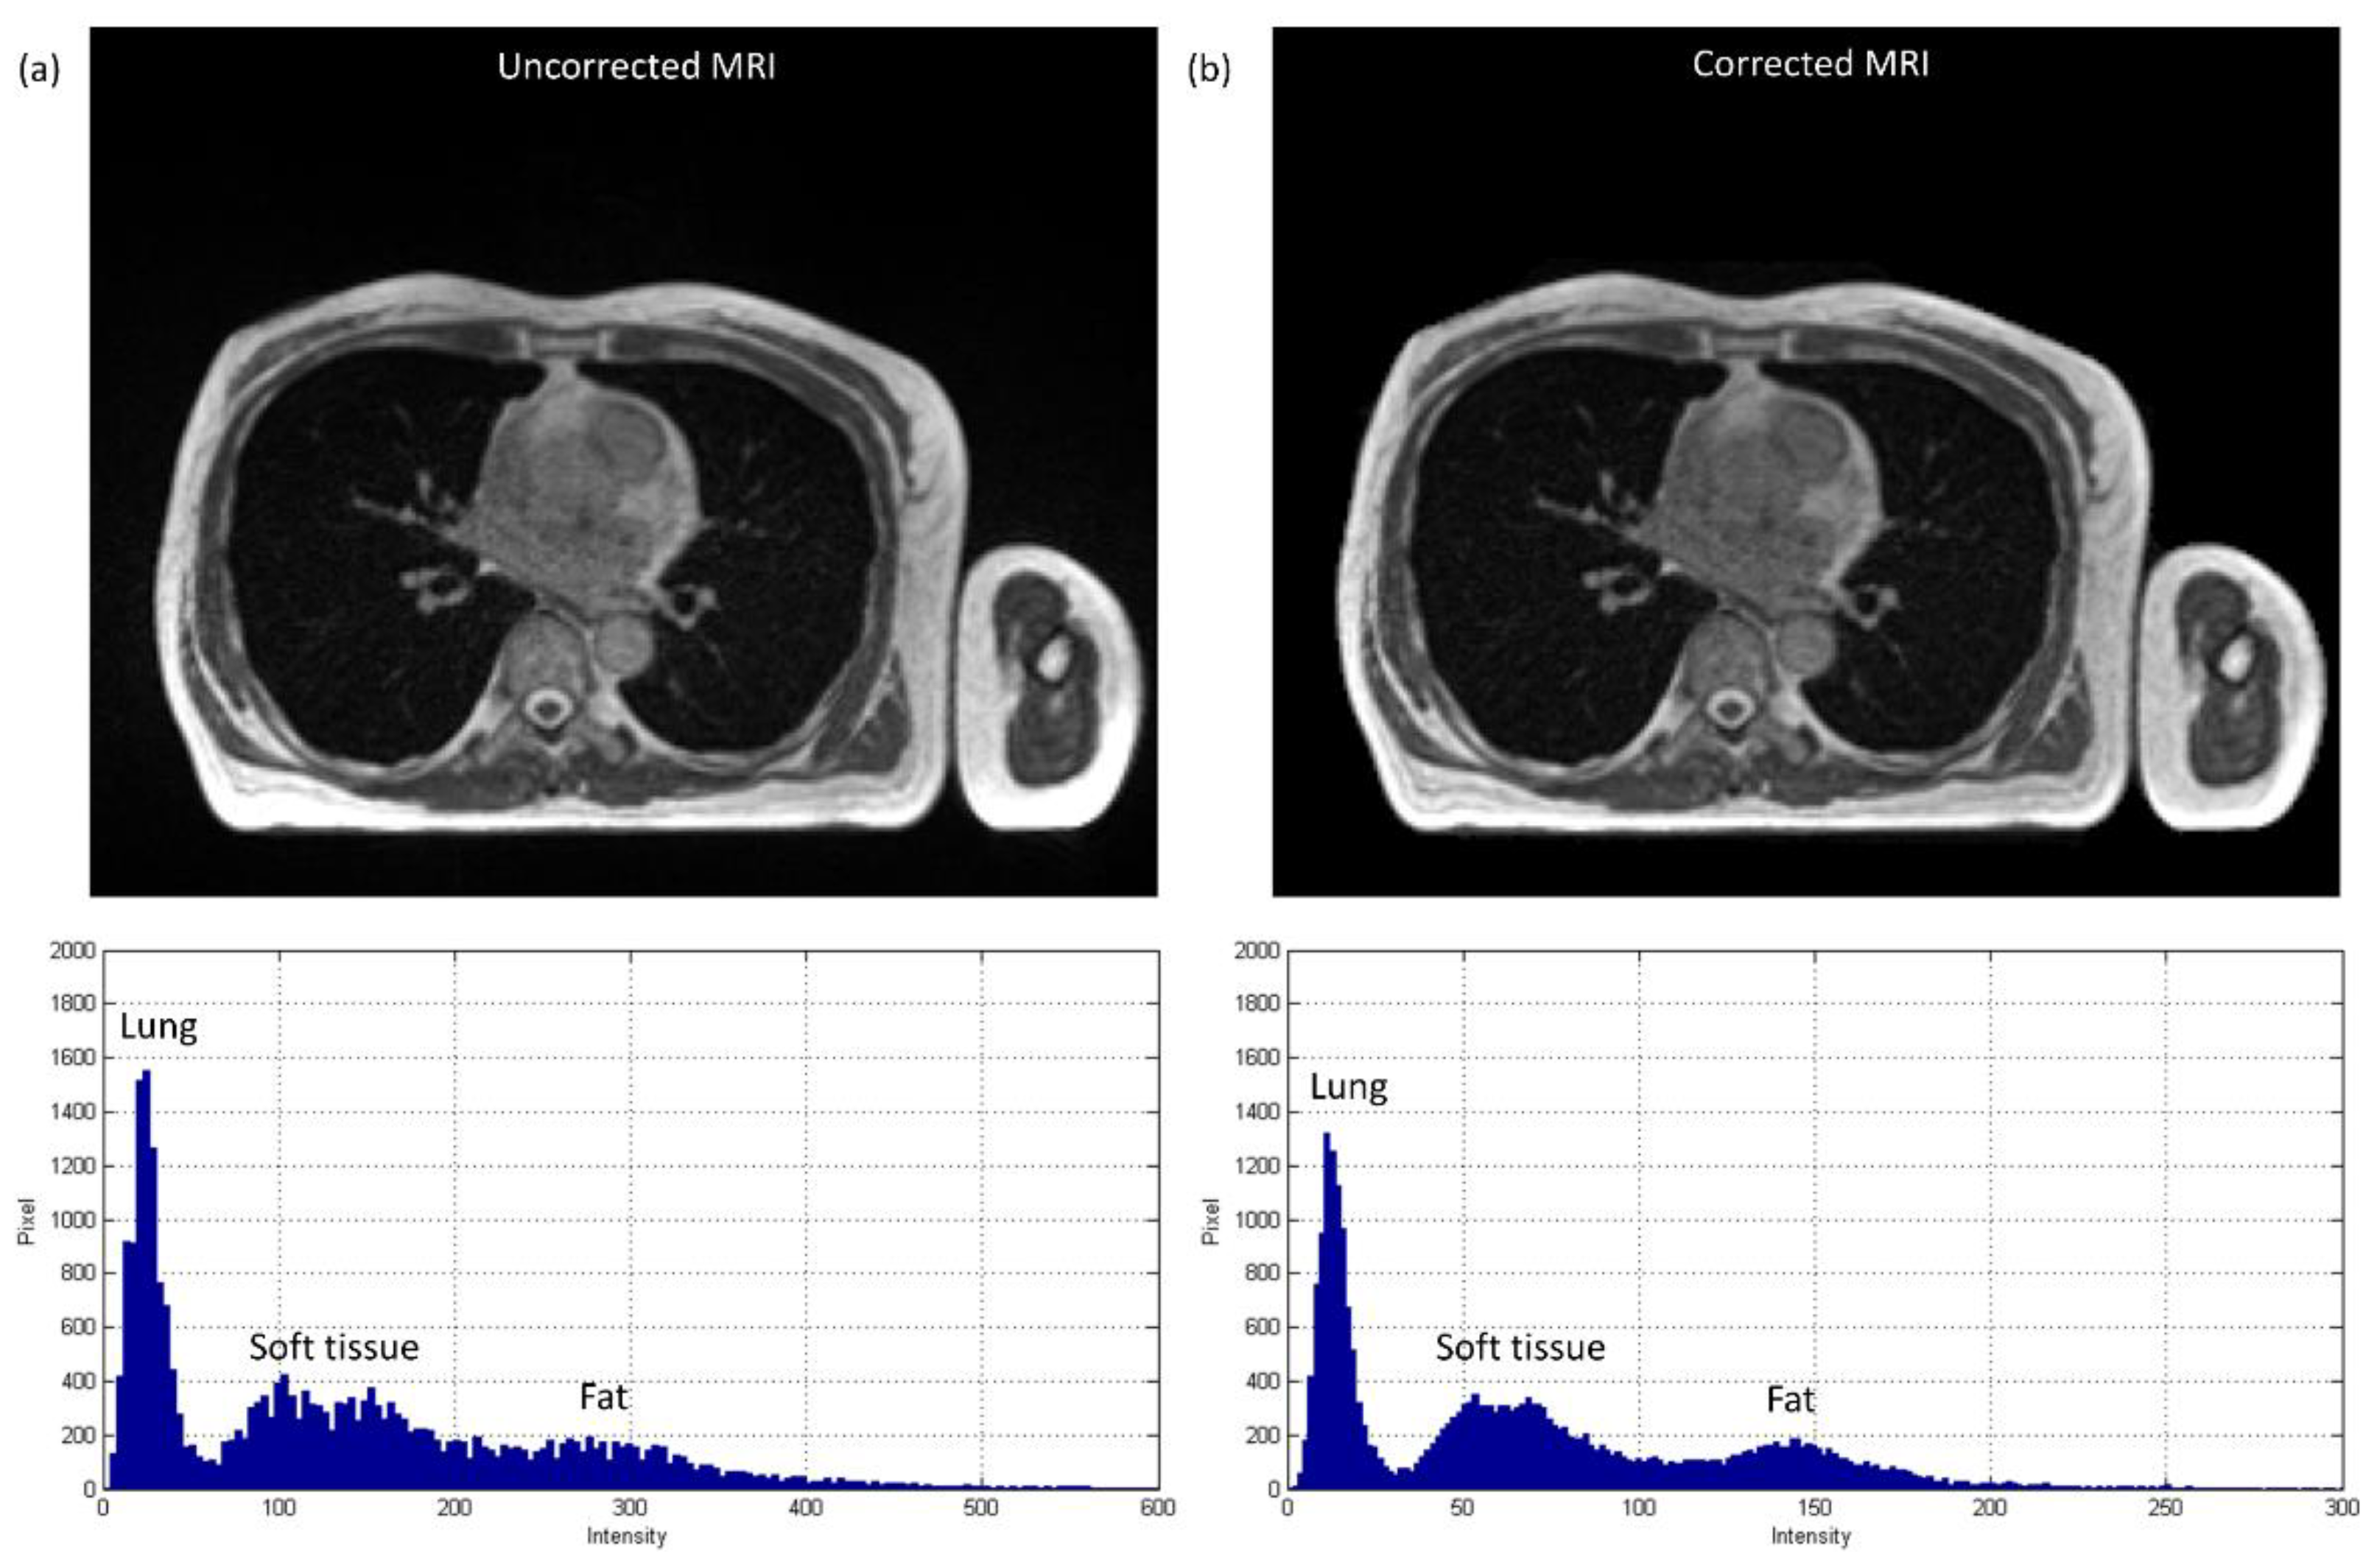

3.1. Chest Imaging for Cancer Treatment